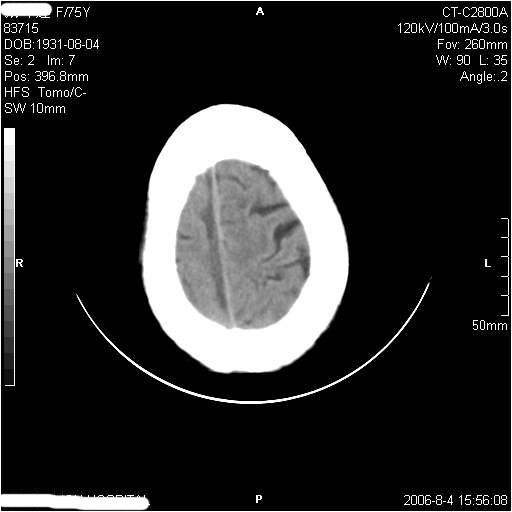

左侧偏瘫3天.

1纵裂硬膜下血肿,2双基底节脑软化灶.

1、纵裂硬膜下血肿,2、右侧室前角旁梗塞;3、双基底节脑软化灶.

有摔倒外伤史,另看右侧灰白质界限.

1、该患者从脑实质表现情况看应该年龄较大了,双侧基底节区多发斑片状低密度灶,侧脑室旁白质密度减低,各脑室腔扩大,脑沟裂增宽加深,以上改变符合:皮层下动脉硬化性脑病。

2、上纵裂右侧梭形条状高密度影阴,边缘模糊,周围水肿带环绕,右侧脑室受压变形,有摔倒外伤史,多考虑:纵裂硬膜下血肿。